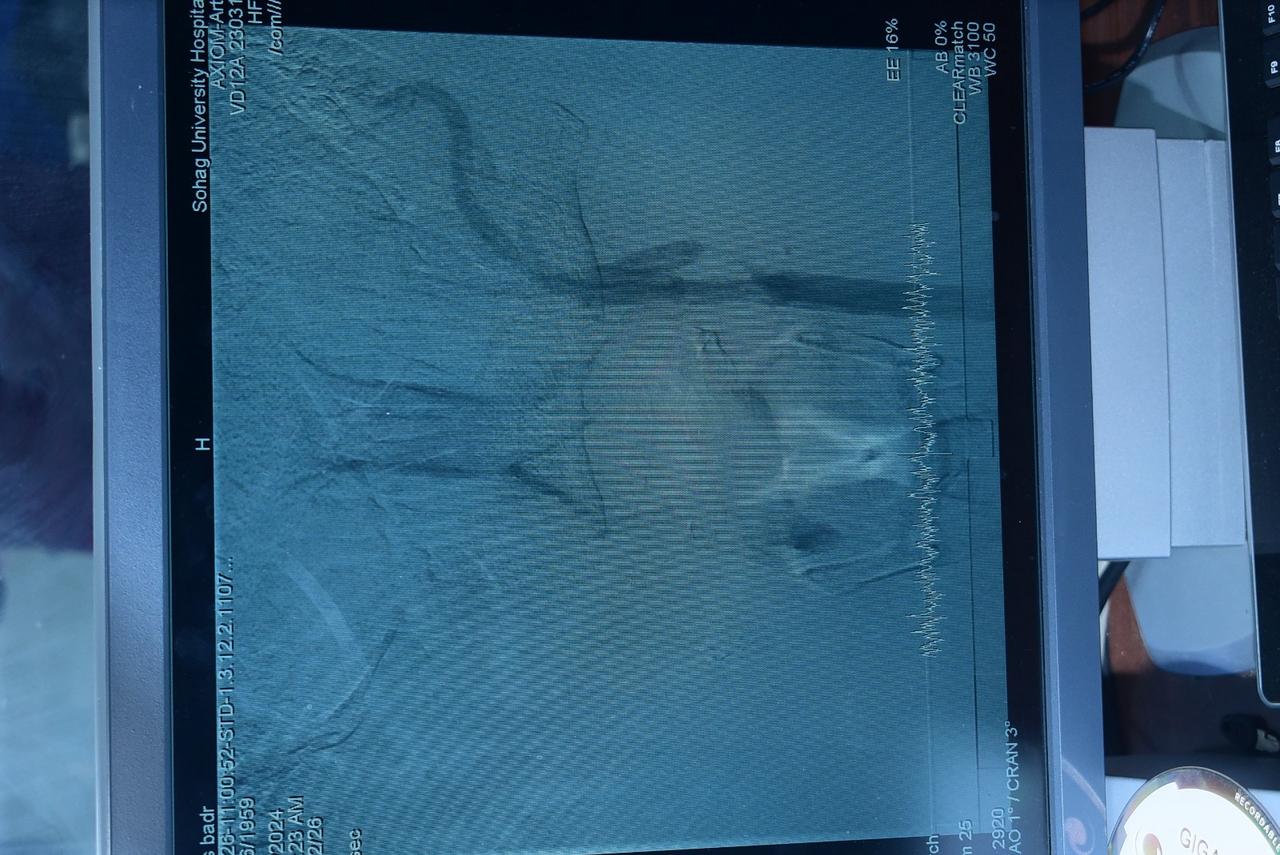

جامعة سوهاج تحقق إنجازًا طبيًا جديدًا وتطلق وحدة القسطرة المخية لخدمة الصعيد

أكد الدكتور حسان النعماني، رئيس جامعة سوهاج، أن وحدة القسطرة المخية بالمستشفى الجامعي تُعد الأولى من نوعها في جنوب الصعيد، حيث تواصل تقديم خدماتها الطبية المتطورة في تشخيص وعلاج أمراض الأوعية الدموية بالمخ. وأضاف أن الوحدة عادت للعمل الشهر الماضي بعد تركيب جهاز قسطرة حديث بتكلفة 17 مليون جنيه، مما يتيح للمرضى تلقي العلاج دون الحاجة إلى السفر لمسافات طويلة.

وأشار الدكتور أحمد كمال، المدير التنفيذي للمستشفيات الجامعية بجامعة سوهاج، إلى أن الوحدة استقبلت خلال الشهر الماضي 6 حالات طارئة تتراوح أعمارهم بين 20 و45 عامًا، حيث خضعوا لعمليات دقيقة باستخدام تقنية القسطرة المخية، ما ساهم في إنقاذ حياتهم وتقليل مخاطر السكتات الدماغية وتمدد الأوعية الدموية.

بدوره، وجه الدكتور عابدين خيرالله قاسم، رئيس قسم جراحة المخ والأعصاب بجامعة سوهاج، الشكر لإدارة الجامعة على دعم الوحدة، مشيرًا إلى أن تقنية القسطرة المخية تعد من أحدث الأساليب العالمية في علاج الجلطات الدماغية وتمدد الأوعية الدموية، حيث تتيح إزالة الجلطات وإصلاح التمددات الشريانية دون جراحة تقليدية، مما يعزز فرص التعافي السريع ويقلل معدلات الإعاقة الناتجة عن السكتات الدماغية.